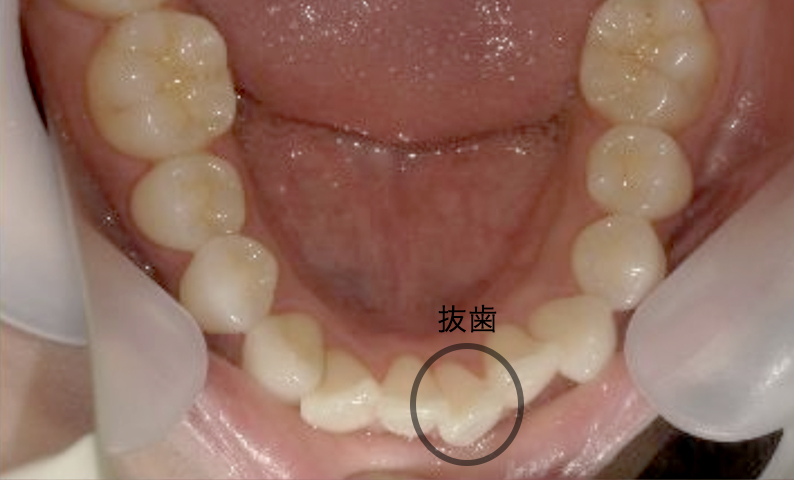

症例_024 上下顎の部分矯正

治療期間:13ヶ月金額:51万円+税女性前歯のガタガタ八重歯